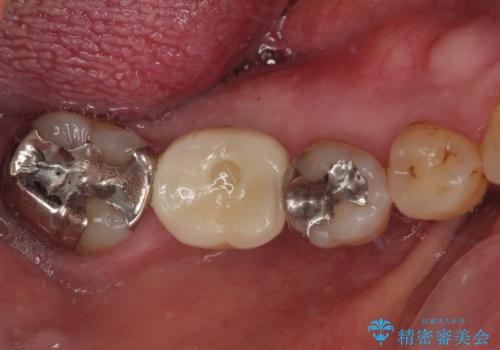

割れて揺れている奥歯 抜歯即時・早期埋入インプラント治療